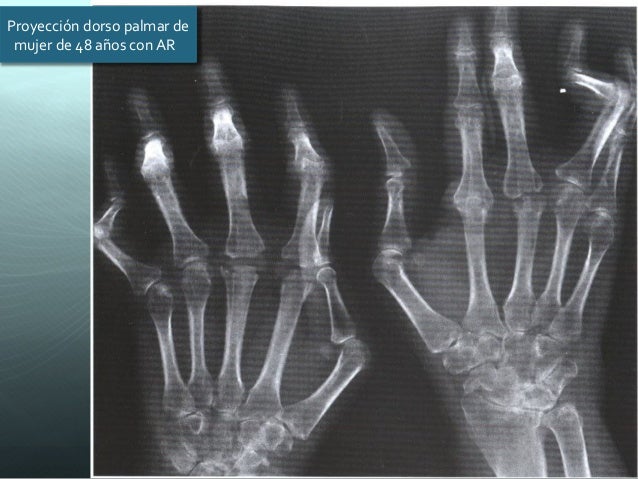

RADIOGRAFÍA

disminución espacio articular

quistes subcorticales

bordes imprecisos